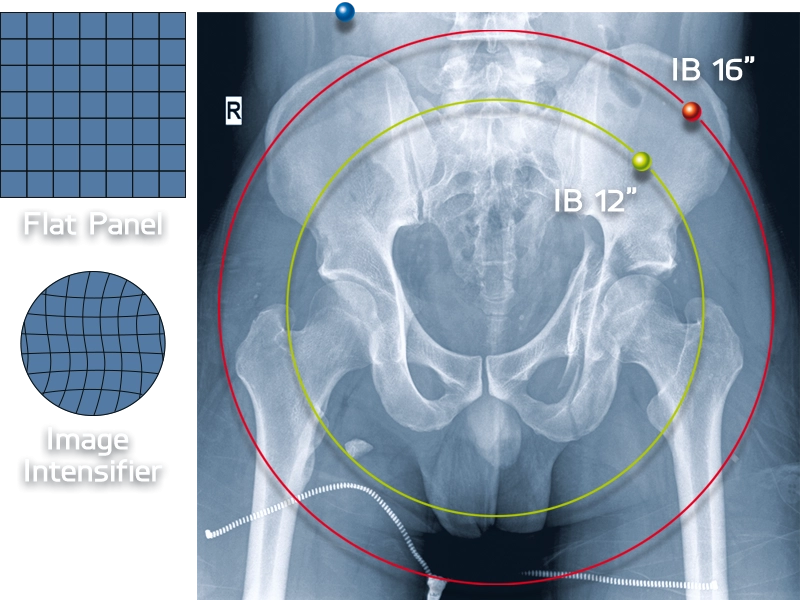

Skaitmeninis vaizdavimas: Apollo EZ gali būti sujungtas su Diva-D arba Diva-HDE skaitmeninio vaizdavimo sistemomis, kurios turi 1K x 1K kameras, 12-bit technologiją ir iki 25 kadrų per sekundę fluoroskopijos greitį.